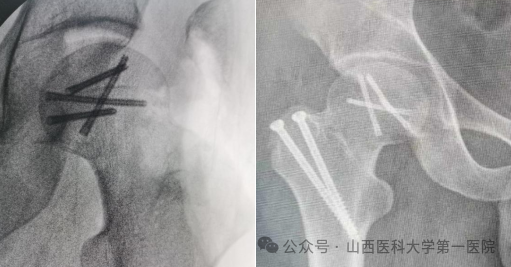

外侧切口,外科脱位入路,显露可见游离股骨头骨块约1/4

精确解剖复位后2.5空心埋头钉固定,复位股骨头脱位及大转子截骨块